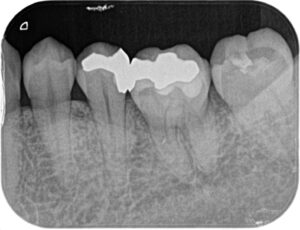

レントゲンを確認で撮りました。段差はなく、非常に適合良いです。